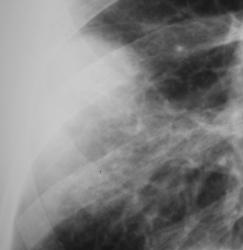

Среднедолевой синдром.

Пациент взят на контроль после расшифровки флюорограмм. Произведено дообследование в прямой и правой боковой проекциях. После проведения исследования направлен к терапевту, выставлен диагноз "Правостороняя среднедолевая пневмония".

Валентин Львович! На время я бы оставил заключение "правосторонняя среднедолевая пневмония". Далее рентгенконтроль и дообследование, при отсутствии динамики.

Да оно и осталось (правостороняя среднедолевая пневмония). Просто случай назван среднедолевым синдромом с учетом некоторых ньансов.